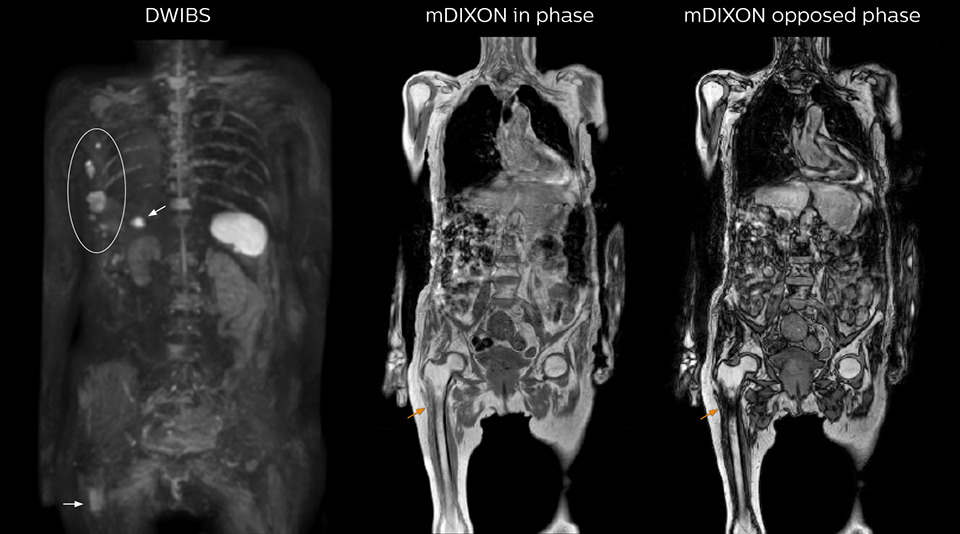

“When we limited the scan coverage to the area from neck to femur, we could fit more clinical information in approximately the same scan time. So, we added coronal mDIXON, sagittal T1-weighted, and sagittal STIR sequences to our examination, instead of performing only axial DWIBS and coronal single-shot TSE scans.” The single shot T2-weighted TSE images are used for morphology and compared to DWIBS images to identify T2 shine-through. Sagittal STIR images are used in patients with inflammation or bone metastasis.

“mDIXON FFE allows us to quickly get information we need to assess the presence of fat. That gives us more information when we need to diagnose bone lesions, and when we are asked to judge fat-containing lesions such as hepatocellular or renal carcinoma,” Dr. Nobusawa says. “The mDIXON fat images can help us to differentiate fatty bone marrow from bone lesions. This is especially useful in elderly people, who tend to have fattier bone marrow. The water images provide a high signal-to-noise ratio in the intestinal canal, which is valuable for visualizing lesions in the colon,” he says.

Kawasaki Sawai Hospital’s whole body protocol also includes an mDIXON FFE sequence. Because mDIXON provides images for four contrast types – water only, fat only, in-phase and out-of-phase – from a single acquisition, it is useful in many ways.